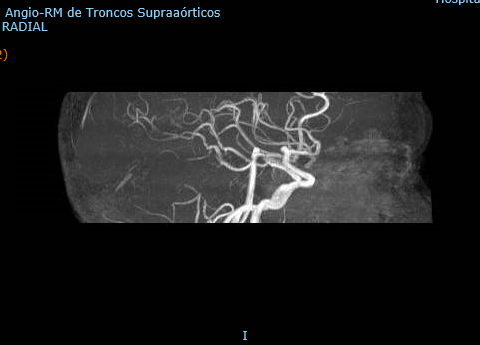

Ecografía Doppler de Troncos Supraórticos

Eje derecho: Velocidad sistólica (cm/s) Carótida Interna (CI) 300; Carótida Común (CC) 64. Relación CI/CC 4,7. Velocidad Diastólica Final (VDF) en la CI 79. Estenosis superior al 70%. Placa heterogénea, irregular, hiperecoica y calcificada. Subclavia normal. Distancia bifurcación normal. Se visualiza CI distal sin alteraciones.

Eje izquierdo: Velocidad sistólica (cm/s) CI 120; CC 92. Relación CI/CC 1,3. VDF CI 30. Estenosis inferior al 50%.

Conclusiones: Eje derecho con abundante ateromatosis de contenido mixto en carótida común y bulbo carotídeo. Estenosis de carótida derecha superior al 70% y estenosis de carótida izquierda inferior al 50%.